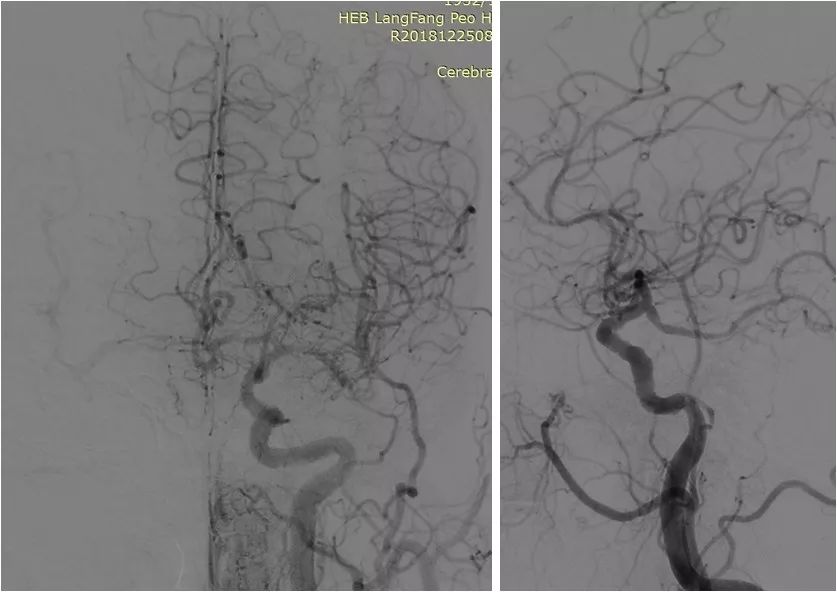

DSA:右颈内动脉C6段重度狭窄;双侧胚胎型大脑后动脉;左椎动脉V1段迂曲,V4段重度狭窄;右椎动脉纤细,V4段以远显影欠佳(图3-6)。

图5

图6